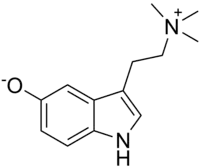

| Bufotenidine | Amphibians | 5-O− | (CH3)3 | 3-[2-(trimethylazaniumyl)ethyl]-1H-indol-5-olate | 487-91-2 | |